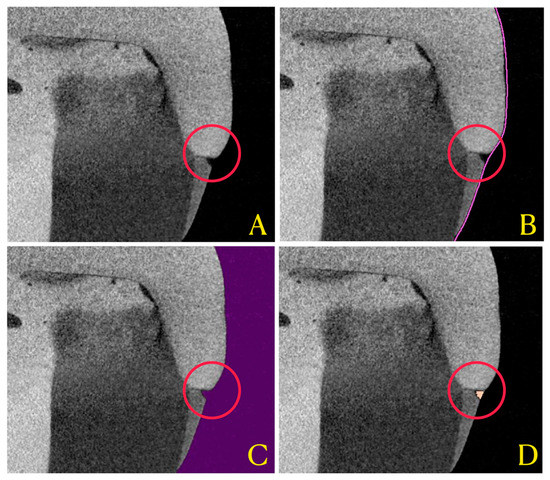

2.3. Micro-CT Scanning

2.7. Tridimensional Marginal Gap Analysis